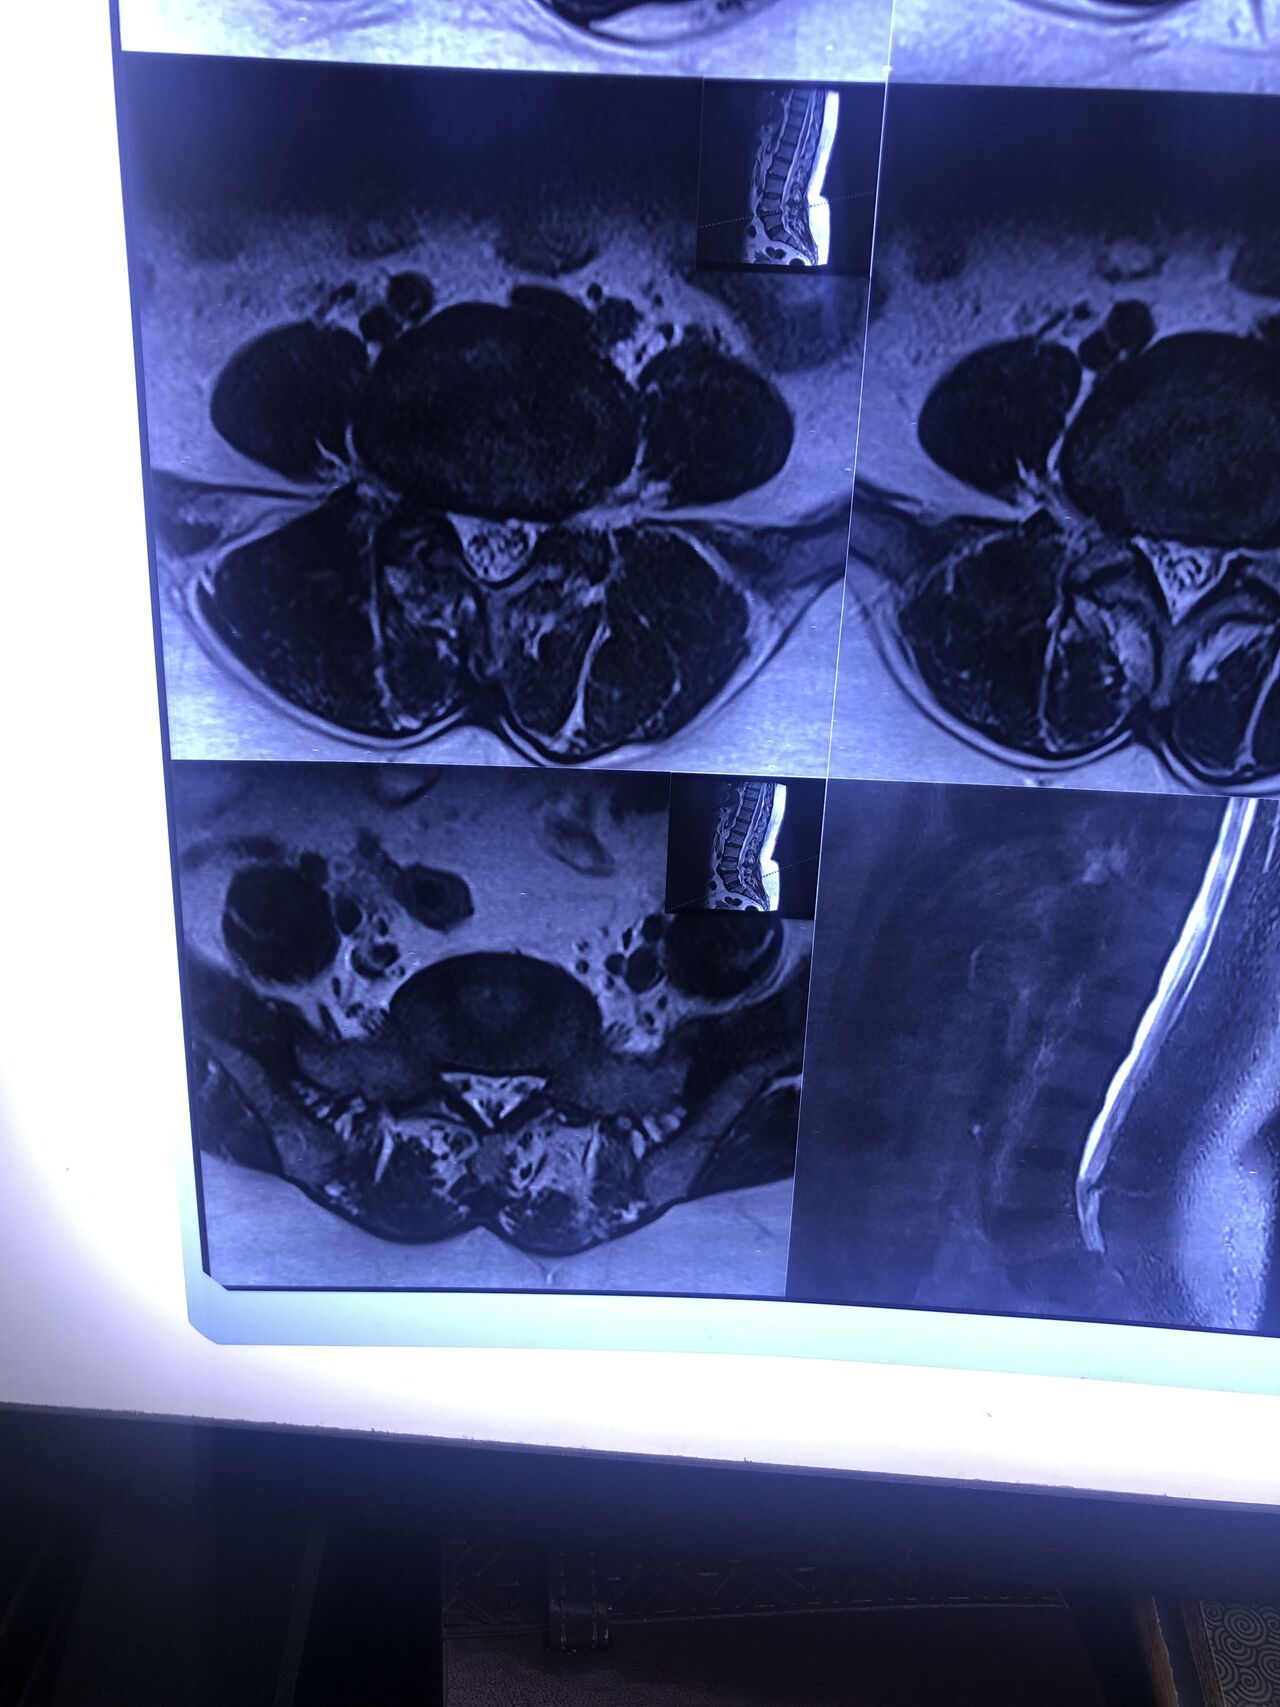

L4-L5 level:

sever L4-5 canal stenosis mainly due to FL hypertrophy?

CSF block. Mild L3 retrolisthesis, facets hypertrophy bilateraly causing L and R IVF stenosis, disc hyperbule

40 yrs old male patient presented to my office who had severe R gluteal pain and radicular pain along R L5-S1 now pain has reduced by 80% in his motor exam had R big toe L5 motor reduced to 4+\5 and R S1 DTR was 0 while L S1DTR was 1+

We did EMG/NCV which showed Mod- sever R L5 S1 irritation without any active axonal loss

I had to decide to refer him for surgery or not patient didn’t have any treatment meanwhile

I ordered new L/S mri

I posted his new mri and old mr

Which was 20 days ago and have posted all below

The first 12 mris had been done 20 days ago

After those first 12 MRIs i have posted new MRIs which were done yesterday

After seeing his new mri and emg/ncv and getting sure his neurological deficit is not active and progressing i told patient he doesn’t need surgery at this time and released him with some advices and exercises